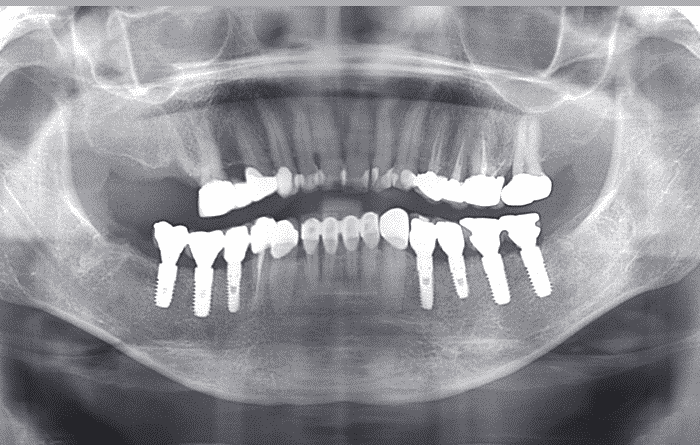

단순 임플란트 치료

단순 임플란트 치료는

뼈이식 등의 추가적인 처치 없이 단순히

뼈에다 구멍을 내고 나사를 식립하는

방식의 치료입니다.